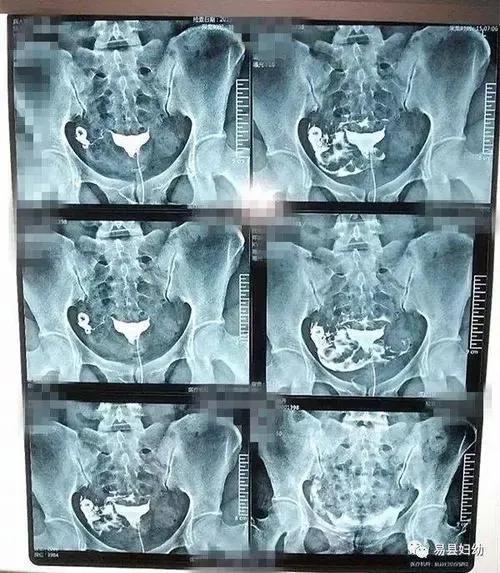

经过几个月的愈合,支原体仍然没有怀孕。老公安慰我,有没有都无所谓。其实他看着单位几个女同事年纪大了,生了二胎,心里挺羡慕的。他有意无意地嗫嚅着,是不是在环内时间长了,输卵管堵塞了。是的,我也一直担心这个。看完网上做造影的各种阵痛,一个下午我还是鼓足勇气,躺在那张冰冷的桌子上,医生喊开始,然后我按下按钮慢慢推药。那种感觉就像拿着冰刀慢慢插进我的身体,又冷又痛。记得有网友说痛了就没意义了,我以为结束了。但一个小时后,医生拿着检查片告诉我,还挺顺利的。你看,药很快就扩散了。我放心了。